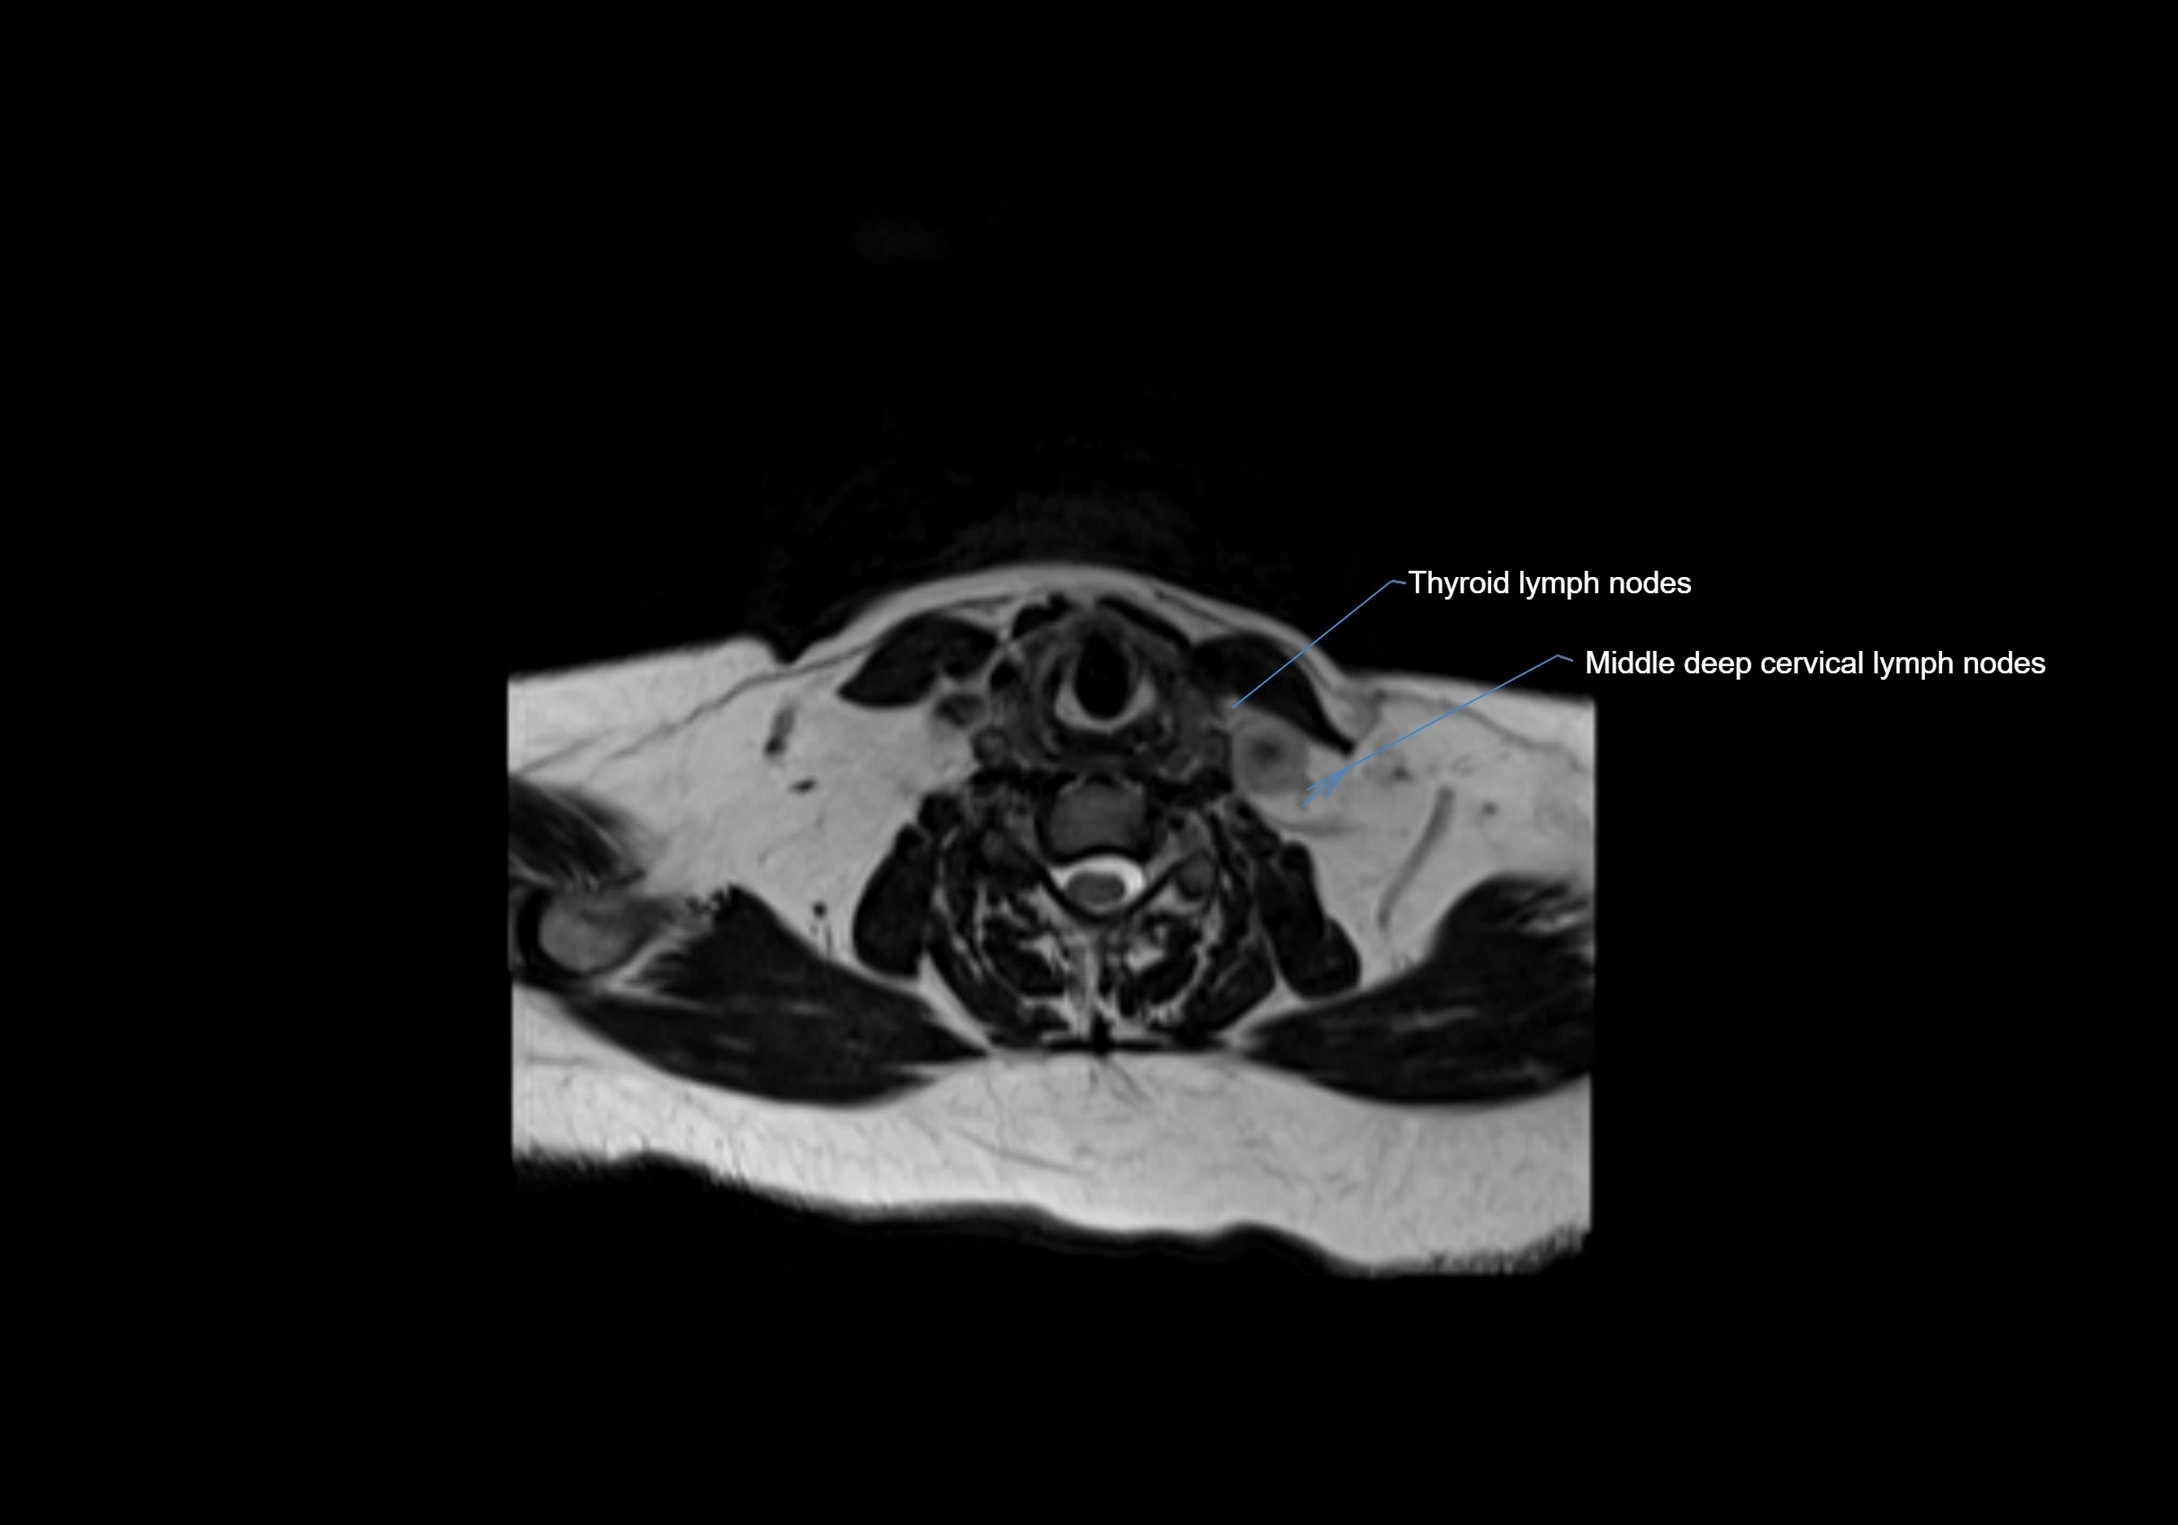

Accessory lymph nodes

Accessory lymph nodes are small, secondary lymph nodes located along the main facial and cervical lymphatic chains, often adjacent to primary lymph nodes, such as preauricular, submandibular, or occipital nodes. They are typically less than 5 mm in diameter, embedded within subcutaneous fat or connective tissue, and may be variable in number and location. These nodes provide additional filtration and immune surveillance for lymph collected from the face, scalp, and neck regions. Accessory lymph nodes are usually non-palpable in healthy individuals but may enlarge in response to infection, inflammation, or metastasis, making them clinically significant.

Location

• Found along primary lymph node chains, including preauricular, submandibular, parotid, and occipital regions

MRI images

image